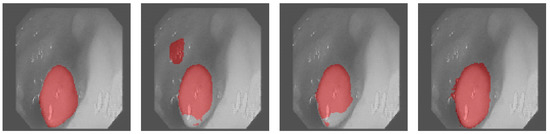

3.4. Results Obtained on the Colonoscopy Dataset